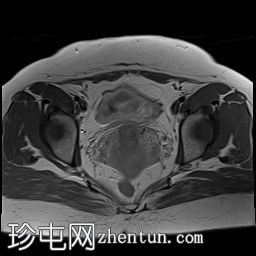

轴位

STIR序列

4.jpg

可见子宫外腹腔内妊娠囊,内含胎儿组织。

该妊娠囊向后推移子宫,并与剖宫产瘢痕凹陷处紧密相连。

该妊娠囊与相关肠袢无法分离。可见其与性腺血管密不可分,且性腺血管明显突出。

胎盘位于妊娠囊后方,紧贴子宫前壁。

沿妊娠囊下缘可见一处异质性局灶性积液,最大轴向尺寸约为 8.4 × 5.5 cm,T1 加权像呈异质性高信号,T2 加权像呈异质性中等信号,T1 脂肪抑制序列未见信号下降,提示为血液成分。该积液压迫膀胱。

可见周围脂肪间隙呈条索状改变。

左侧卵巢无法辨认。

右侧卵巢未见实性或囊性肿块。

子宫体积增大,后倾,子宫内膜厚度约 1 cm,子宫下段前壁可见局灶性变薄(既往子宫瘢痕)。子宫连接区完整,未见肌层肿块。可见子宫内膜腔边缘有血性分泌物。